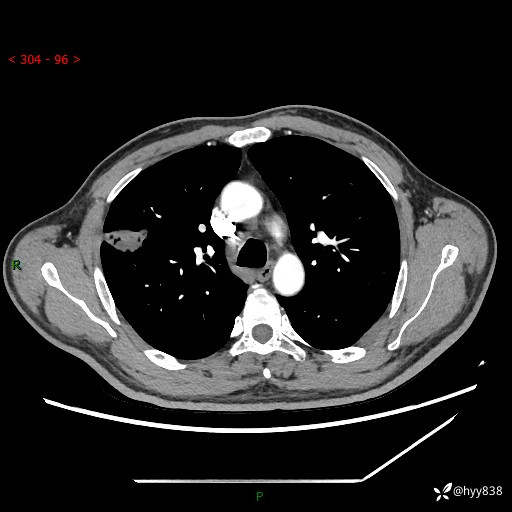

现病史:患者2天前体检完善胸部CT提示:右上肺团块影,炎症可能,肿瘤性病变不除外,冠状动脉钙化,无咳嗽、咳痰,无寒战发热,无恶心、呕吐等其他特殊不适,未予以特殊治疗,现为明确病变性质来我院就诊,门诊以“肺肿物性质待查”收入我科。 起病以来,患者精神、饮食、睡眠可,大小便正常,体力体重较前无明显变化。

胸部CT平扫+增强